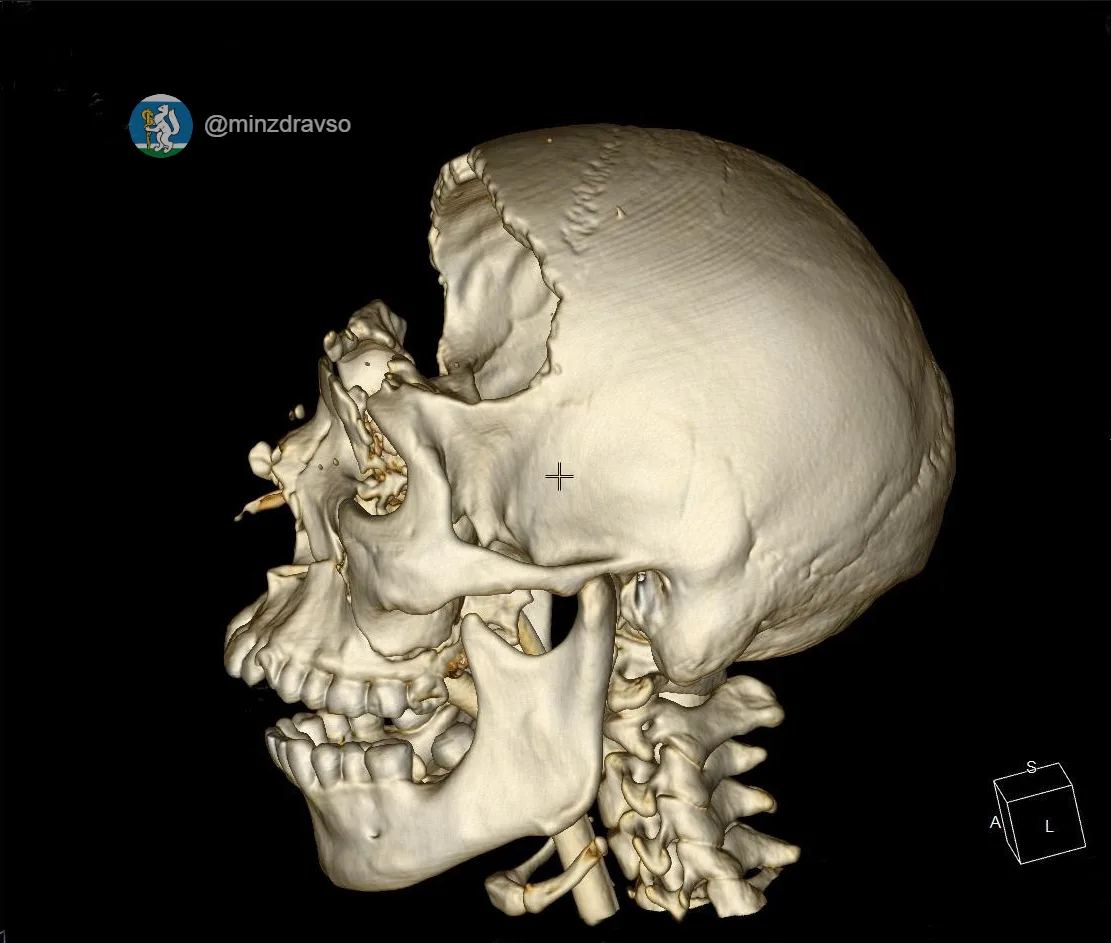

Татьяна Савинова: «Десять месяцев — и маленькая пациентка снова танцует»

Знаете, есть истории, которые напоминают: медицина — это не только диагнозы и протоколы. Это вера. Вера врачей в пациента. Вера родителей в чудо. И вера ребёнка в то, что боль не навсегда.

Вот Алиса. Обычная девочка: школа, друзья, мечты. И вдруг в 11 лет — тяжёлая травма позвоночника. Перелом.

Сегодня рада сообщить, что спустя 10 месяцев юная жительница Режа успешно прошла финальный этап долгого и сложного лечения — операцию по удалению импланта.

Благодаря слаженной работе команды врачей-травматологов и нейрохирургов Уральского института травматологии и ортопедии им. В.Д. Чаклина, невероятной силе духа юной пациентки и поддержке родителей жизнь девочки снова полна радости.

Несмотря на ограничения после операции и длительное ношение шейного корсета, который разрешили снять только в феврале 2026 года после полного сращения позвонков, Алиса продолжила заниматься в хореографической школе, чтобы быть в форме и не отстать от своих сверстниц. Родители поддерживали дочь на каждом этапе, и эта помощь стала неотъемлемой частью пути к выздоровлению.

Недавняя операция по удалению металлоконструкций — завершающий аккорд в этой непростой истории. В знак признательности Алиса приготовила творческую композицию для своего лечащего врача, нейрохирурга Антона Пьянкова. Сувенир стал для доктора сюрпризом и лучшей наградой за труд.